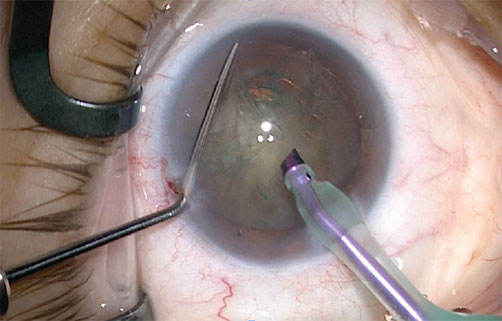

An incision of about 2 mm made through the cornea and an opening created in the envelope of the lens.

An ultrasound probe is then inserted into the lens. Ultrasound sprays the proteins of the lens and softens it, making it easier to remove. This step called “phacoemulsification”.

In most people, the crystalline lens replaced by an artificial lens, introduced into the lens envelope. The lens introduced is selected according to the patient. Depending on the case, the lens can correct myopia, hyperopia, astigmatism, and presbyopia.